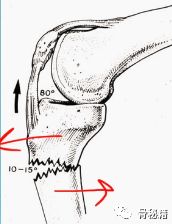

我们先来分析一下胫骨近端的解剖,容易出现哪些移位,一屈曲膝关节,则容易出现外翻,屈曲,上移。

最佳的进针点的位置,关节面的最前缘处,正位位于外侧髁间嵴的内侧。

讲完进针点的要点,下来就要谈谈体位,半伸直体位植钉技术要点,可以使股四头四放松,不再牵引胫骨近端的骨折块,基本就复位了,最好是将远端置放在一个水平的垫子上,这样基本力线也维持好了,正侧位也比较好透视。同时可以采用内侧髌旁入路,使得髌骨外侧半脱位时进针,应用保护套筒较好的进行保护相应的关节面和韧带软组织。